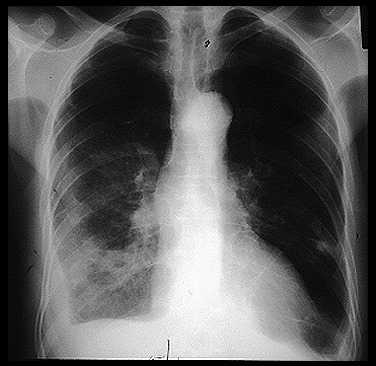

Emergency Medicine And First Aid A Free Ebook Online Pneumonia Diagnosis And Treatment

Emergency Medicine And First Aid A Free Ebook Online Pneumonia Diagnosis And Treatment